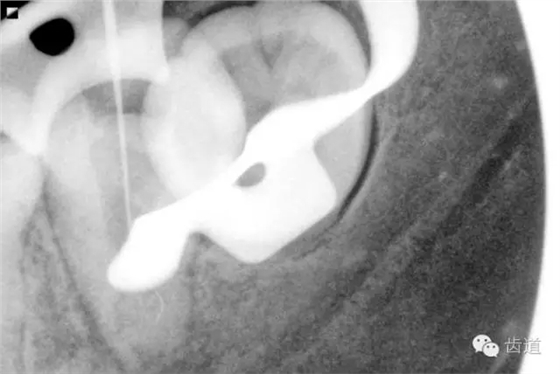

2. 術(shù)前X片

可見37根管影像清晰,根中上三分之二粗大,根尖三分一分為近遠(yuǎn)中兩根管,形態(tài)均呈弧形,根尖周膜連續(xù)性中斷,根尖周透射影明顯